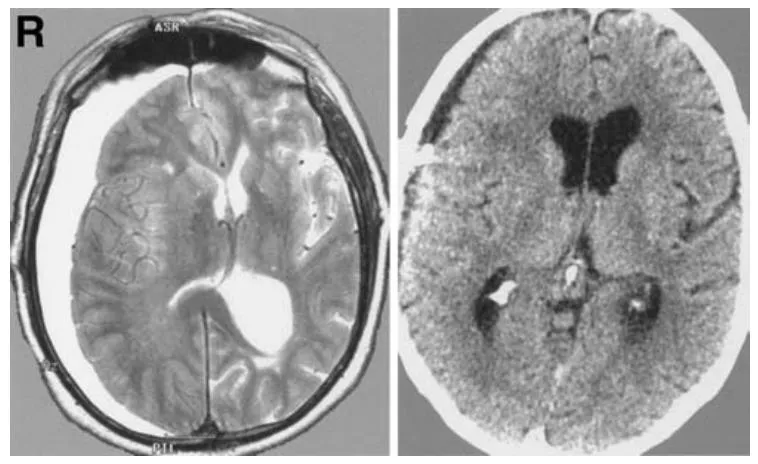

术后第三个月,患者出现了硬膜下水瘤,临床症状包括头痛、共济失调以及左侧肢体无力;磁共振成像检查证实右侧大脑半球存在硬膜下积液(图5左)。医疗团队先后实施了两次钻孔引流手术,第二次手术中置入了临时硬膜下引流管,此后患者病情好转并顺利出院。

在第二次手术结束两个月后,患者因相同症状再次入院。计算机断层扫描检查提示硬膜下水瘤复发。随即,医生为患者施行了硬膜下-腹腔分流术。术后患者恢复情况良好,计算机断层扫描显示硬膜下水瘤已完全消失(图5右)。

图5 左图:轴位T2加权磁共振成像显示右侧大脑半球存在硬膜下水瘤;右图:硬膜下-腹腔分流术后轴位计算机断层扫描图像